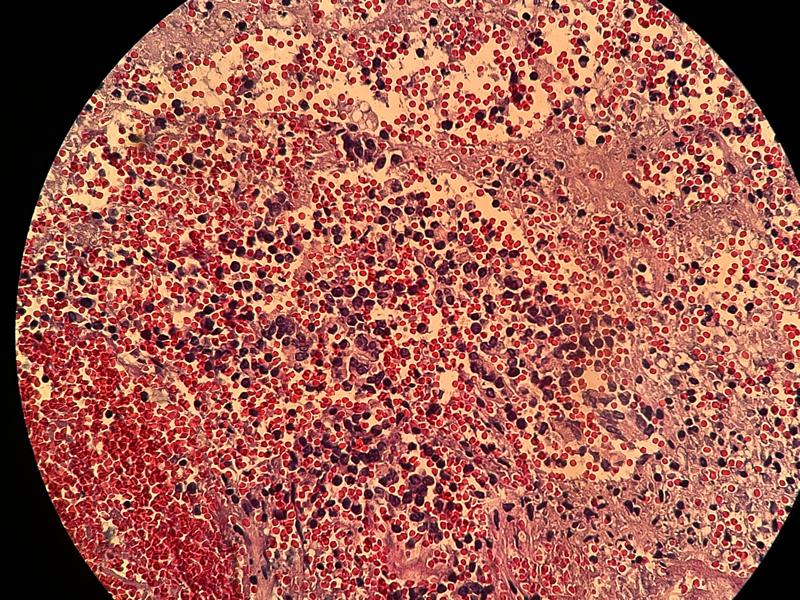

宫内膜组织

性别

女

年龄

37

临床诊断

功血

一般病史

阴道不规则流血20天

标本名称

大体所见

灰白灰红膜样物质一堆,约2.1✖️1.2✖️0.4

倾向内膜息肉

组织形态符合子宫内膜息肉,表面有乳头的那些区域要鉴别乳头样化生和表面浆液性肿瘤,免疫组化可能会有帮助。